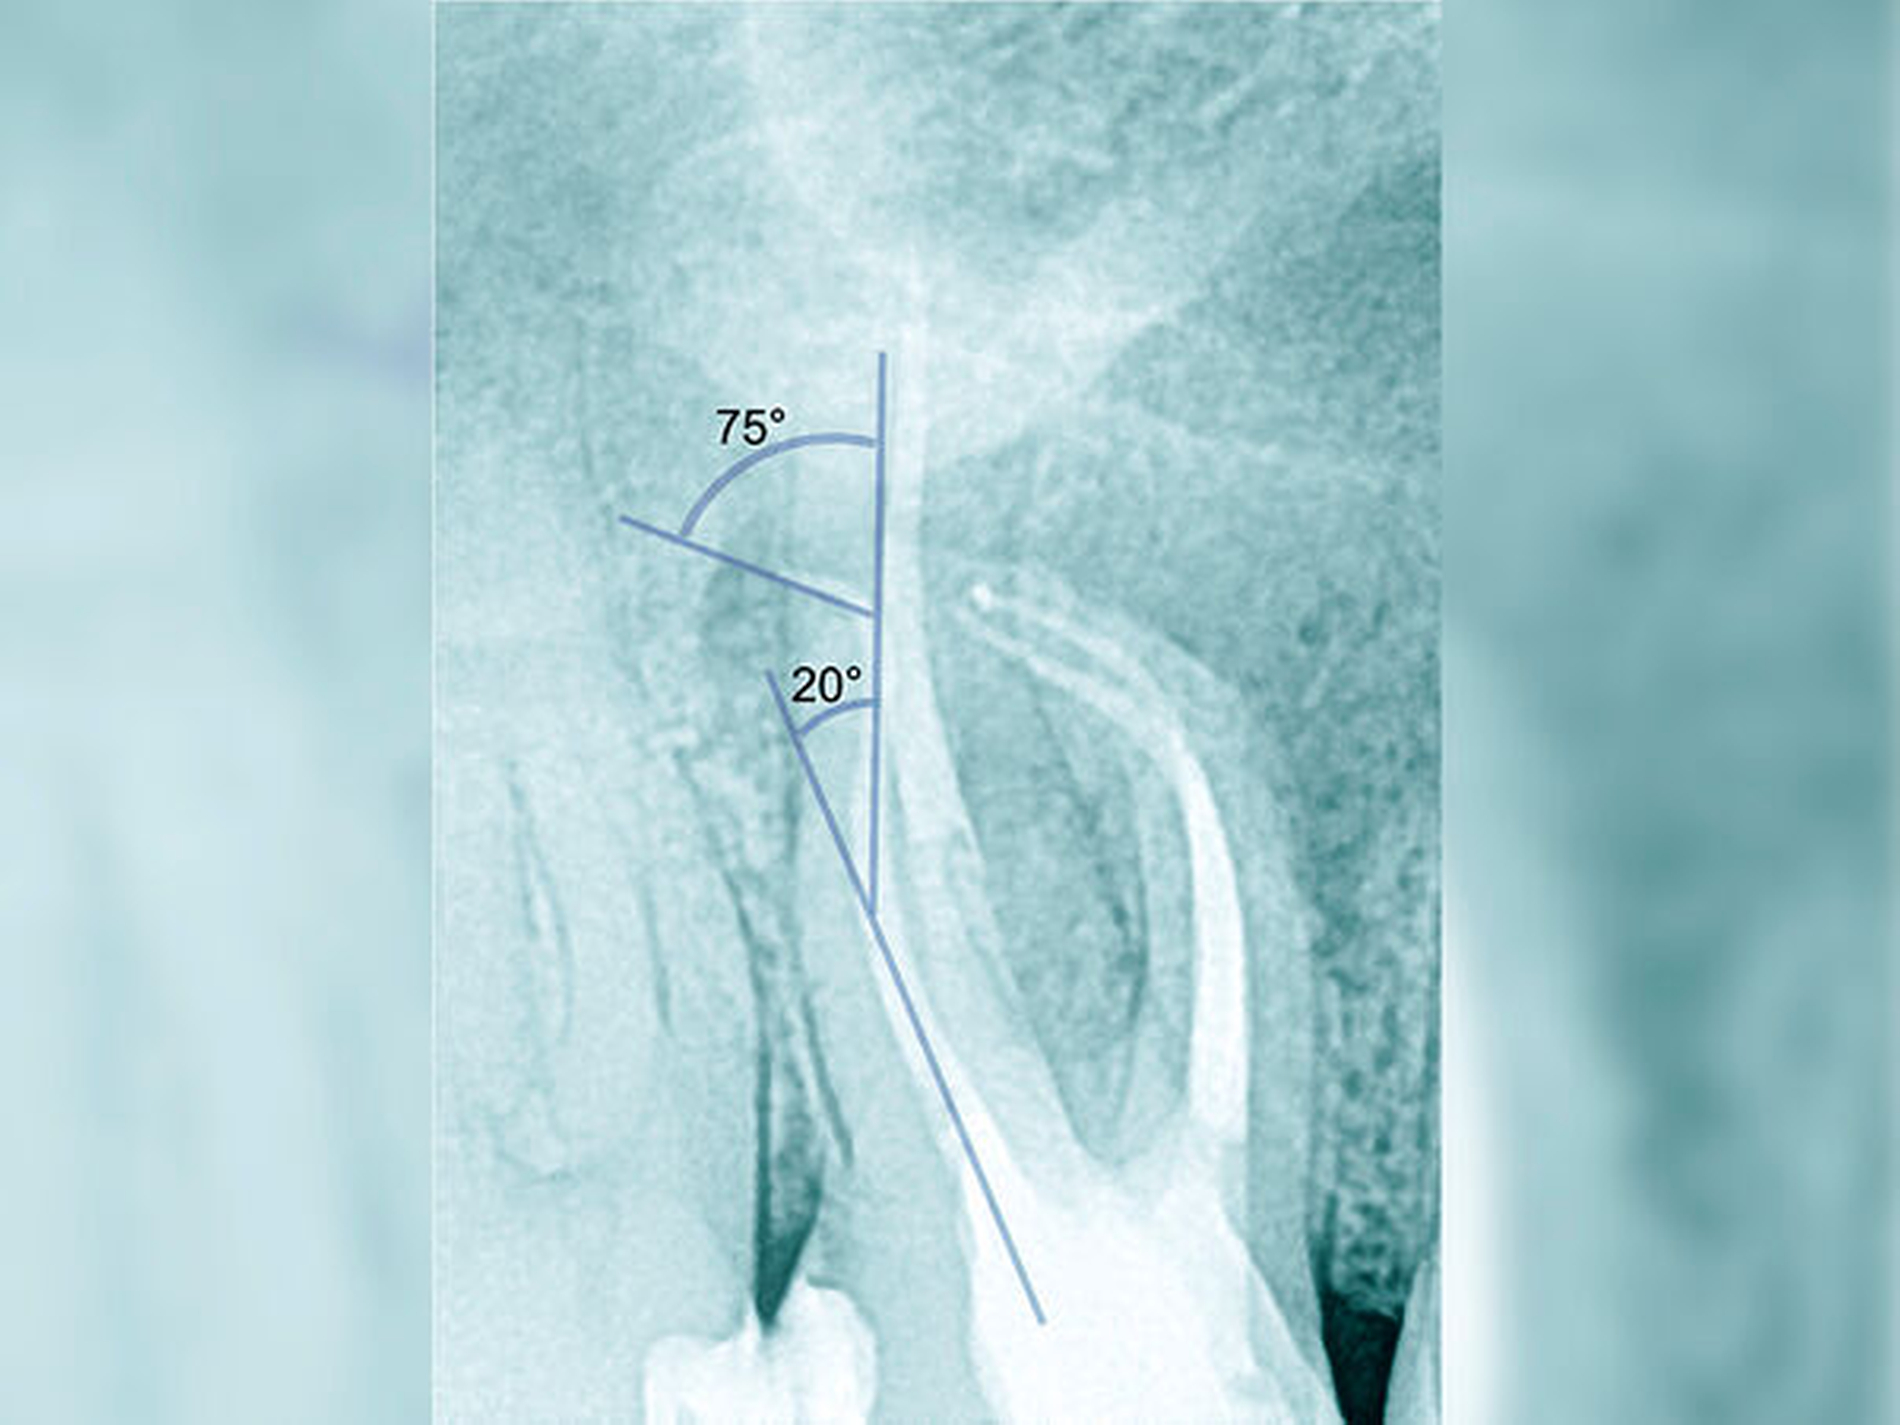

Die Schwierigkeit in der Therapie nimmt zu, wenn die Wurzelkanalkrümmung mehr als 30 Grad beträgt, der Krümmungsradius abnimmt (enge Krümmung) oder Mehrfachkrümmungen vorliegen [Duke et al., 2015; Pedulla et al., 2020]. Typisch für Mehrfachkrümmungen sind vor allem mesiale Wurzelkanäle unterer Molaren (Abbildung 4).

Sollte eine Konfluenz beider mesialer Wurzelkanäle am unteren Molaren vorliegen, kommt es zu einem abrupten Richtungswechsel und Instrumente können leichter frakturieren oder Stufen präparieren, so dass die Arbeitslänge nicht mehr erreicht werden kann.